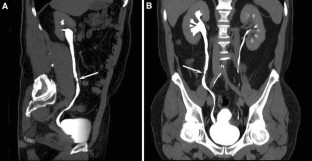

The combination of EU + CT correctly diagnosed 38 out of the 39 cases with a sensitivity of 97%. Correct diagnosis was established in all malignant cases (n = 17) but one benign case consistent with blood clots in the upper urinary tract was incorrectly diagnosed as a multicentric urothelial carcinoma. Sensitivity, specificity, and accuracy for the diagnosis of the underlying cause with EU + CT was 100%, 95%, and 97%, respectively. The final diagnoses were: urothelial carcinoma (n = 10), stone disease (n = 10), bladder tumor (n = 4), benign post-treatment ureteral stenosis (n = 4), ureteral invasion (n = 3), benign bladder disease (n = 2), urinary tract infections (n = 2), crossing vessels (n = 1), ureteropelvic junction obstruction (n = 1), retrocaval ureter (n = 1), and blood clots in the upper urinary tract due to bleeding renal metastasis from lung cancer (n = 1).

Combined EU and CT study allowed correct diagnosis of the underlying cause of delayed excretion or upper urinary tract dilatation in 97% of cases. The combination of EU and CT provides diagnosis reducing time and radiation.